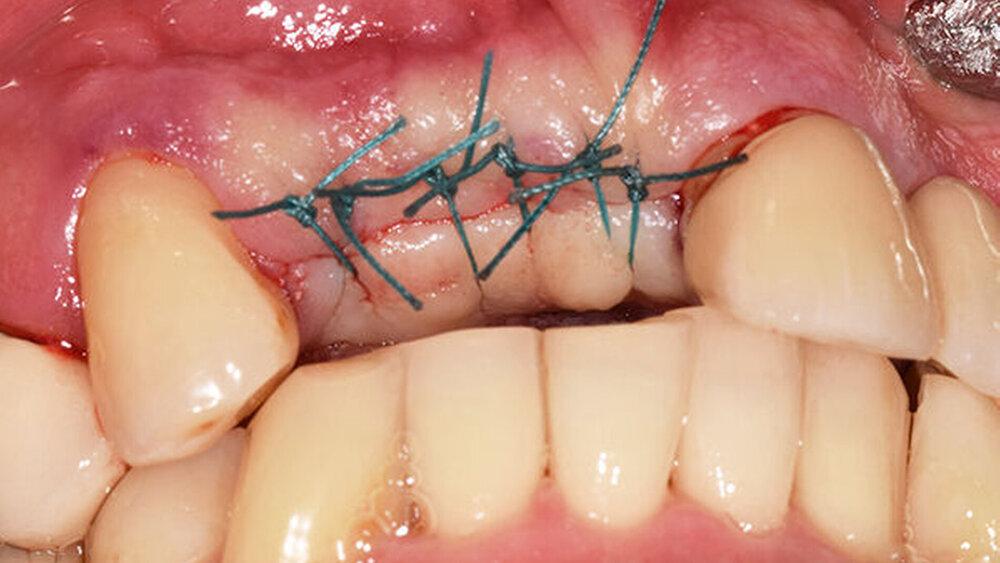

Die Implantatschulter wurde leicht supracrestal platziert, sodass die prothetische Plattform zirka 2 mm unter dem Weichgewebeniveau zu liegen kam (Abb. 5). Lateral der Implantatschulter wurden die autologen Knochenspäne gemischt mit feinkörnigem BioOss (Geistlich) eingebracht und die Implantate über den Klickmechanismus in der Innenkonfiguration des Implantats mit der PEEK-Abdeckkappe verschlossen (Abb. 6). Die CERALOG Hexalobe-Implantate sind im Halsbereich weniger rau als im enossalen Bereich, damit sich das Weichgewebe im Bereich des Implantathalses und die Knochenzellen an der mikrorauen Struktur im enossalen Bereich optimal anlagern können. Das Augmentat wurde mit einer Bio-Gide-Membran (Geistlich) abgedeckt. Es lag ausreichend keratinisierte Gingiva vor, sodass keine Weichgewebeverdickung erforderlich war. Der Wundverschluss erfolgte ohne Periostschlitzung (Abb. 7), um die Ernährungsphysiologie des Weichgewebes nicht zu verschlechtern und eine Verschiebung der Mukogingivalgrenzlinie nach koronal zu vermeiden. Der Lappen ließ sich für den spannungsfreien Wundverschluss tunnelierend ausreichend weit nach subnasal präparieren. Im Anschluss an die Implantatinsertion wurde die Valplast-Prothese basal ausgeschliffen, um augmentationsbedingte Druckstellen zu vermeiden. Die postoperative Röntgenkontrolle (Abb. 8) zeigt eine anatomisch exakte Implantatpositionierung nach Schablonenvorgabe.

Während der komplikationslosen Heilungsphase betreute der Hauszahnarzt den Patienten. Wie geplant, erfolgte nach zwölf Wochen die Implantatfreilegung (Abb. 9) in unserer Praxis. Das Weichgewebe zeigte sich in einem blutungs- und reizfreien Zustand. Mit einer leicht palatinal orientierten crestalen Kieferkammschnittführung wurden die Implantate freigelegt, das Weichgewebe wurde nach vestibulär verdrängt (Abb. 10) und die Gingivaformer wurden aufgesetzt. Um einen quantitativen Zugewinn von keratinisiertem Gewebe zu erhalten, wurde die Naht zwischen den Implantaten nicht komplett geschlossen. Die Implantate zeigten sich klinisch und röntgenologisch sicher osseointegriert (Abb. 11).